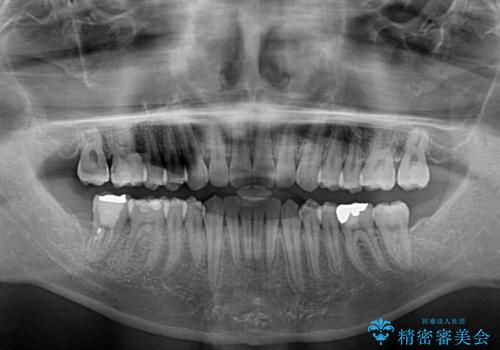

- 口元の突出感を治したいとのことで来院された患者様です。

上下顎ともにIPR(歯と歯の間を削る)と歯列全体の拡大によって口元が引っ込むように設計し、インビザラインにより治療を行うこととしました。

抜歯をして口元を下げなければならないほど出っ歯ではなかったため、少しずつ治療ゴールを変更しながら仕上げていきました。

気になっていた前歯の飛び出した印象は、最終的にはスッキリと引っ込み、大変満足していただきました。